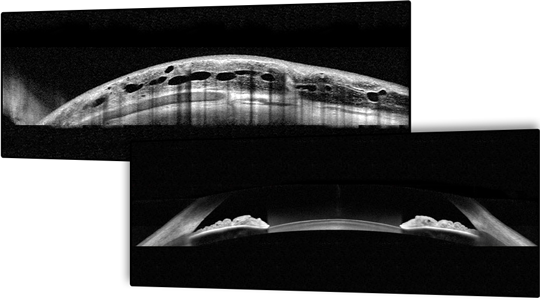

Anterior Segment Module

Yüksek çözünürlüklü ön segment görüntüleme: SPECTRALIS® Ön Segment Modülü ile elde edilen yüksek çözünürlüklü görüntüler, korneanın katmanlarını ayrıntılı bir şekilde gösterir ve kornea kalınlığının değerlendirilmesine yardımcı olur. Modül ayrıca, verimli bir ön kamara açısı değerlendirmesi için açıdan açıya görüntüleme sunar ve skleral yapıların detaylı görüntülerini sağlar.